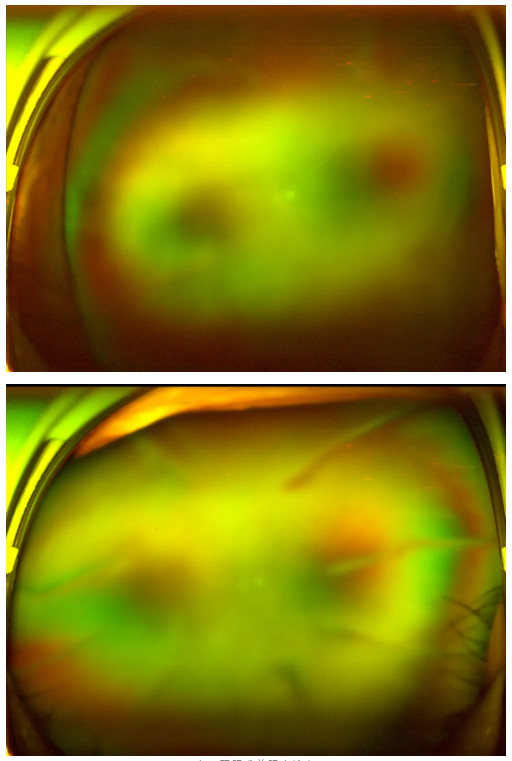

老王雙眼術前眼底檢查

“別灰心,好好配合治療,你還是有很大機會能恢復部分視力的。”王曉波主任的話像一顆定心丸,讓老王懸著的心得以放松。在醫(yī)生的指導下,老王先積極穩(wěn)定血糖,為后續(xù)治療打下堅實基礎,隨后多次轉(zhuǎn)機重返廈門眼科中心辦理入院,準備接受針對性治療。

王曉波主任告知老王:術后復查眼底顯示,其糖尿病視網(wǎng)膜病變并不嚴重,因此視力得以得到明顯改善與提升。當初堅持治療、不輕言放棄,是非常正確的選擇!

糖尿病視網(wǎng)膜病變